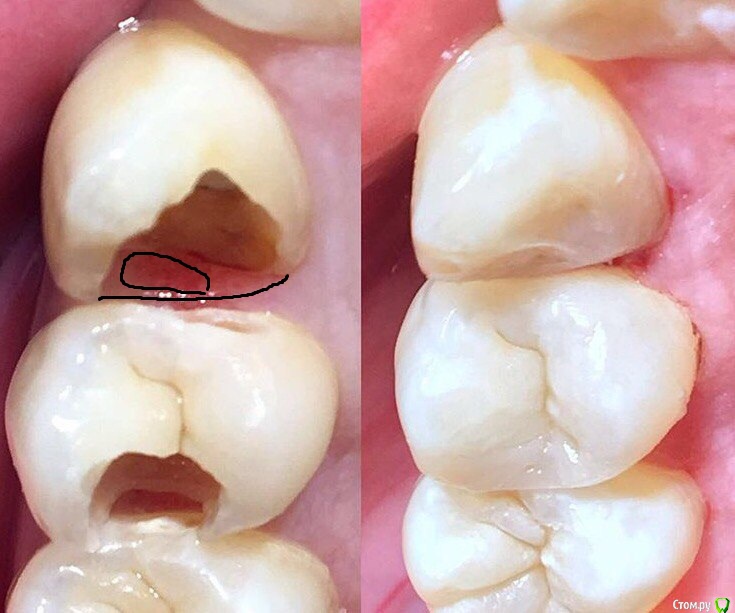

Wrestrus66 Опубликовано 12 октября, 2016 Поделиться Опубликовано 12 октября, 2016 У меня вот вопрос... Как сюда поставить матрицу и восстановить контакт??!? есть ли фото.. то что там матрицу клиньями прижать и тефлоном это я знаю, но как на деле это выглядит.. Ведь там вечно будет кровить... 2 Ссылка на комментарий

Kolchanov Опубликовано 12 октября, 2016 Поделиться Опубликовано 12 октября, 2016 Как сюда поставить матрицу и восстановить контакт? Судя по фото вы как-то выкрутились. Как? И смоделировано с выпендрежем, респект! Ссылка на комментарий

Ker Опубликовано 13 октября, 2016 Поделиться Опубликовано 13 октября, 2016 Десна пусть кровит, главное матрицу поставьте плотно и герметично на всём протяжении, в данном конкретном случае это было бы несложно. И да, клык явно в ортопедию, пломбу быстро разобьет и герметичность нарушится. Первое фото после препа? Там точно твердо всё? Ссылка на комментарий

Pan Опубликовано 13 октября, 2016 Поделиться Опубликовано 13 октября, 2016 на первой фотке полости недопрепарированы, имхо. 1 Ссылка на комментарий